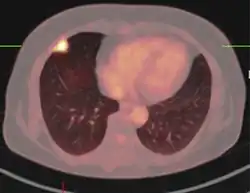

PET scan

FDG-PET study of a 71-year-old woman with a solitary pulmonary nodule (thin arrow) in the left lower lobe near the heart. The scan also revealed abnormal increased activity at the gastro-esophageal junction (thick arrow). The final diagnosis was non-Hodgkin lymphoma at both sites.

If there is an intermediate risk of malignancy, further imaging with positron emission tomography (PET scan) is appropriate (if available). It can be done simultaneously as a CT scan in the form of PET-CT. Around 95% of patients with a malignant nodule will have an abnormal PET scan, while around 78% of patients with a benign nodule will look normal on PET (this is the test sensitivity and specificity).[15] Thus, an abnormal PET scan will reliably pick up cancer, but several other types of nodules (inflammatory or infectious, for example) will also show up on a PET scan. If the nodule has a diameter of less than one centimeter, PET scans are often avoided because of an increased risk of falsely normal results.[15][16][17] Cancerous lesions usually have a high metabolism on PET, as demonstrated by their high uptake of FDG (a radioactive sugar).